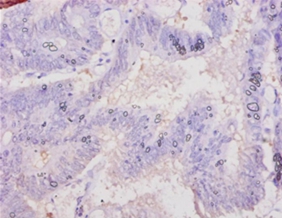

Immunohistochemical analysis of paraffin-embedded human colon cancer using #42120 at dilution of 1:10.